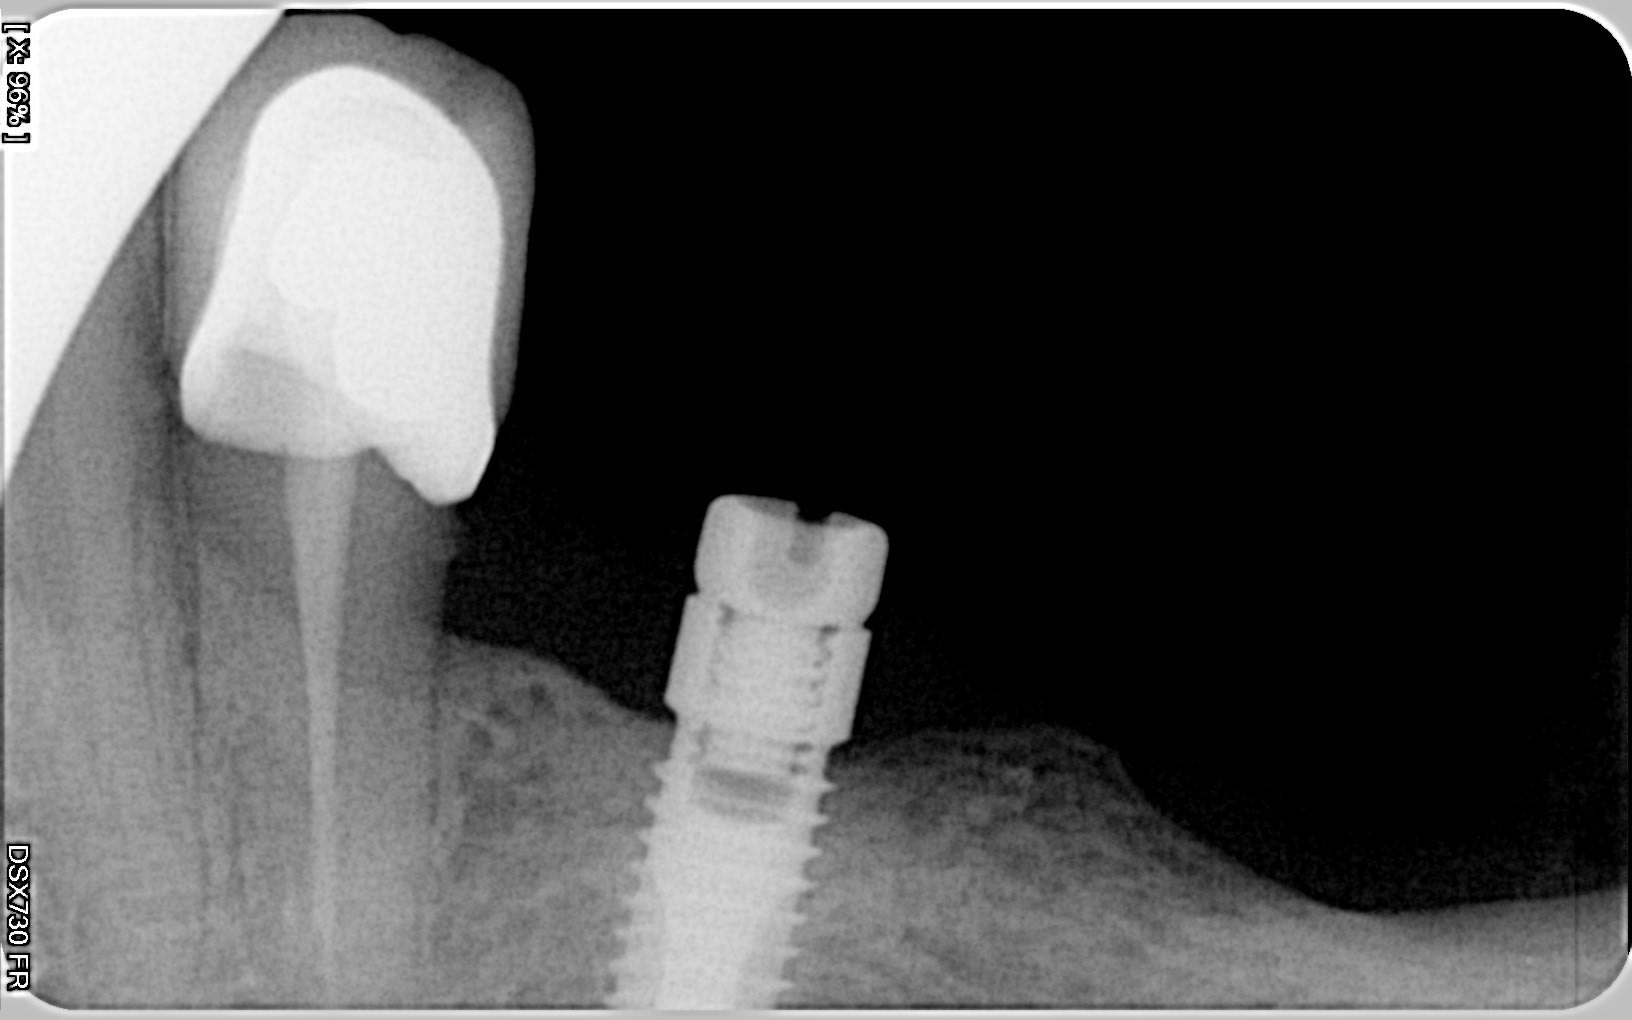

J' essaie vainement de dévisser cet attachement, je pensais que c'était comme le locator mais en fait la clé ne rentre pas, j'ai essayé de dévisser avec un davier sans succès.

C'est certainement un era ( il y a un petit trou sur le coté )mais je ne trouve pas la doc de montage, pouvez vous m'aider ?